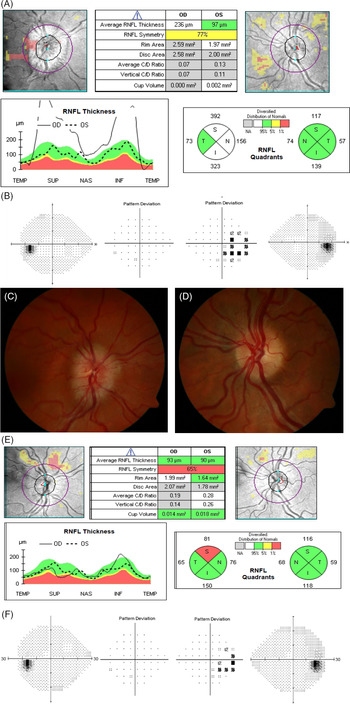

Weight was 192 lbs.; BMI 31 kg/m2. Corrected visual acuity was 20/25 OD and 20/20 −2 OS. Ishihara color plates were 15/17 OD and 17/17 OS. Pupils reacted equally to light without RAPD. Funduscopy revealed Frisén grade 2 optic disc edema in the right eye; the left optic disc appeared normal (Figure 1C and D). Spontaneous venous pulsations were absent bilaterally. Visual fields were full to confrontation. Extraocular movements were full. 24-2 Humphrey visual field testing showed an enlarged blind spot in the right eye (MD + 0.05 dB); the left was normal (MD + 1.73 dB) (Figure 1B). OCT showed an average RNFL thickness of 236 µm OD and 97 µm OS (Figure 1A).

Figure 1: Initial OCT in Case 2 (A) shows an average RNFL thickness of 236 µm OD and 97 µm OS. Initial 24-2 Humphrey visual field testing (B) shows an enlargement of the blind spot in the right eye (MD + 0.05 dB; 4% false-positive errors) with a normal field on the left (MD + 1.73 dB; 0% false-positive errors). Fundus photographs from Case 2 obtained pre-treatment show prominent optic disc edema in the right eye (C) with the absence of edema on the left (D). After 3 months of treatment with acetazolamide OCT (E) demonstrates the improvement of right optic nerve swelling and reduction of retinal nerve fiber thickness with average RNFL thickness of 93 µm OD and 90 µm OS. 24-2 Humphrey visual field testing (F) shows improvement in the enlargement of the right eye blind spot (MD −0.33 dB; 6% false-positive errors) and ongoing normal field on the left (MD + 0.57 dB; 0% false-positive errors).

She was started on acetazolamide 500 mg twice daily and counseled to lose weight. After 3 months, headache, visual blurring, and tinnitus had improved. Funduscopy showed no evidence of papilledema in either eye. Visual acuity was 20/20 –2 OU; Ishihara color plates were 17/17 OU. 24-2 Humphrey visual field testing showed a reduction of the enlarged blind spot (MD −0.33 dB OD, + 0.57 dB OS) (Figure 1F). OCT demonstrated a reduction of RNFL thickness (93 µm OD and 90 µm OS) (Figure 1E). She lost 30 lbs. (BMI 26.1 kg/m2) and acetazolamide was tapered and stopped in 1 year. She has been stable without recurrence of papilledema for 4 years.